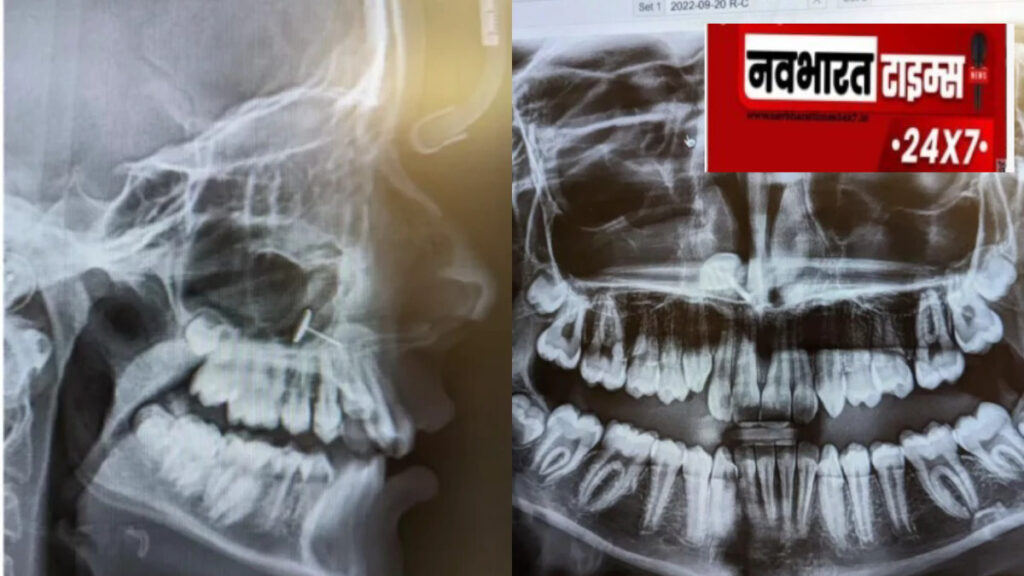

न्यूजवीक की खबर के मुताबिक, ओफीलिया (बदला हुआ नाम) अपनी 13 साल की बेटी को ब्रेसेज की प्रक्रिया शुरू करने के लिए ऑर्थोडॉन्टिस्ट के पास ले गई थीं. यह एक रूटीन विजिट थी, लेकिन एक्स-रे ने सबको चौंका दिया. ओफीलिया ने न्यूजवीक को बताया कि ऑर्थोडॉन्टिस्ट ने एक्स-रे स्क्रीन पर लगाए, और हम सबने एक साथ देखा. कई मिनट तक हम समझ ही नहीं पाए कि ये क्या है.

स्क्रीन पर साफ दिख रहा था कि बेटी की साइनस में धातु का एक छोटा टुकड़ा फंसा हुआ था. मां के लिए यह पूरी तरह रहस्य था, लेकिन उनकी बेटी तुरंत समझ गई कि यह क्या है और वहां कैसे पहुंचा.

जब डेंटल एक्स-रे ने इस राज को उजागर किया, तो ओफीलिया ने अपनी हैरानी को Reddit पर यूजरनेम u/Scared_Category6311 के तहत शेयर किया. उनकी पोस्ट ने तहलका मचा दिया और 73,000 से ज़्यादा अपवोट्स बटोर लिए.

इस घटना का अंत सौभाग्य से पूरी तरह सुरक्षित और दर्दरहित रहा. ओफीलिया ने तुरंत एक ENT (Ear, Nose, Throat) विशेषज्ञ से संपर्क किया, जिन्होंने पहले बेटी के टॉन्सिल्स निकाले थे. डॉक्टर ने लंबी मेडिकल चिमटी की मदद से धातु के टुकड़े को आसानी से हटा लिया. ओफीलिया ने बताया कि मेरी बेटी को कोई दर्द नहीं हुआ और उसने इस प्रक्रिया को बहुत अच्छे से हैंडल किया.इस अनुभव ने ओफीलिया के नज़रिए को थोड़ा बदल दिया. पहले वह नोज पियर्सिंग के सख्त खिलाफ थीं, लेकिन अब उनका रुख नरम हो गया है. उन्होंने हंसते हुए कहा कि शायद इस साल वह अपनी नाक छिदवा ले.